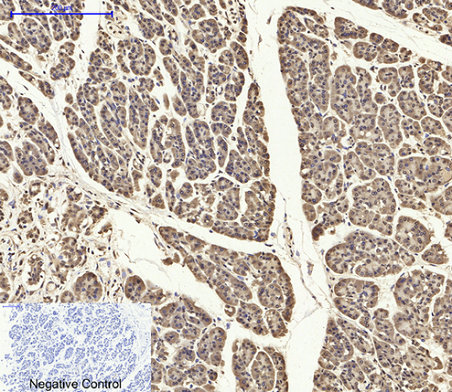

Immunohistochemical analysis of paraffin-embedded Human-stomach-cancer tissue. 1,ASC Polyclonal Antibody was diluted at 1:200(4°C,overnight). 2, Sodium citrate pH 6.0 was used for antibody retrieval(>98°C,20min). 3,Secondary antibody was diluted at 1:200(room tempeRature, 30min). Negative control was used by secondary antibody only.